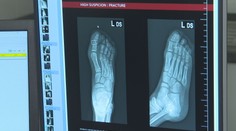

„Vozidlo RV má najvyšší stupeň výbavy zo všetkých záchranárskych vozidiel. Máme výbavu, ktorú iné vozidlá nemajú. To znamená, že máme prenosný sonograf a aj resuscitačný prístroj, čiže prístroj na stláčanie hrudníka. Tá výbava je top. Máme aj lieky, ktoré záchranky nevozia,“ priblížil vedúci lekár Jakub Hamšík.

„Máme viac pomôcok napríklad na zabezpečenie dýchacích ciest. Vozíme dva ventilátory. Jeden z nich je taký štandardný, druhý ventilátor je špeciálny na ventiláciu aj veľmi malých detí, čo nie je bežné,“ vyzdvihla hlavná záchranárka Beáta Macejková.